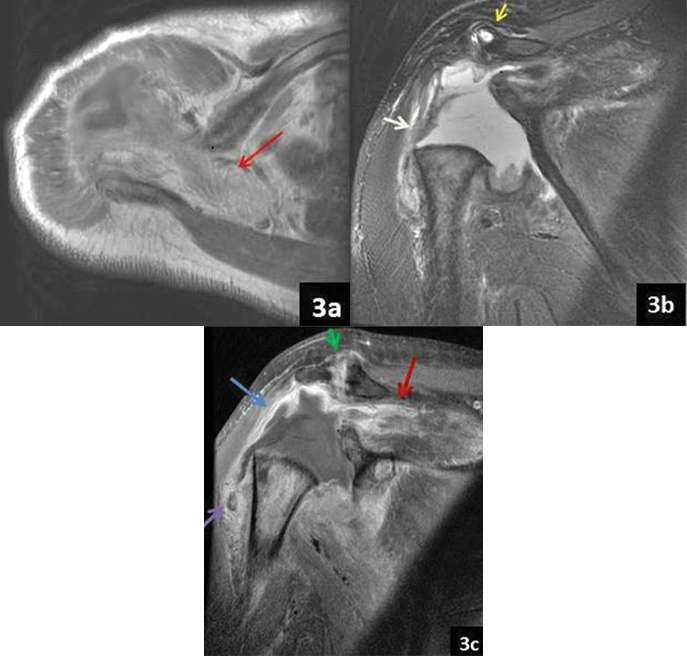

Subsequently, Computed Tomography (CT) and MRI were performed. Unenhanced CT and contrast enhanced MRI showed destruction of head of humerus and glenoid fossa with multiple bony debris within the joint cavity and adjacent muscles with markedly thickened and enhancing synovium and joint effusion [Table/Fig-2,3].

a) Axial T1 image showing fatty infiltration of supraspinatus muscle (red arrow); b) Coronal T2 Fat Sat image showing gross joint effusion with thickened peripheral synovium (white arrow), destroyed humeral head and flattening of glenoid. Subchondral cyst seen within acromion process (yellow arrow); c) Post contrast Coronal T1 fat sat image showing peripherally enhancing synovium (blue arrow), enhancing synovium within acromioclavicular joint with articular surface irregularity (green arrow), hypointense bony debris (purple arrow) and enhancing supraspinatus muscle (red arrow).

Multiple hypointense foci were seen within and surrounding the joint cavity and within triceps muscle on T2 weighted images to suggest bony debris. There was complete involvement with heterogeneous signal of rotator cuff tendons with heterogeneous enhancement of the muscle belly of supraspinatus, infraspinatus, subscapularis, teres minor, triceps and deltoid muscle. Marked fatty degeneration of supraspinatus muscle and mild fatty atrophy of subscapularis and infraspinatus tendon was seen. There was involvement of acromioclavicular joint with cortical irregularity and subchondral cyst in acromion process with joint effusion, thickened and enhancing synovium [Table/Fig-3].